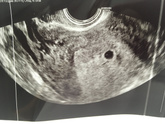

По узи эмбриона все ещё не увидели. ПЯ и желточный мешочек подрос. Гематом или отслоек нет. Гинеколог смотрела говорит все чисто не кровит, а до шейки дотронулась и она закровила. В общем отправили на дневной стационар.